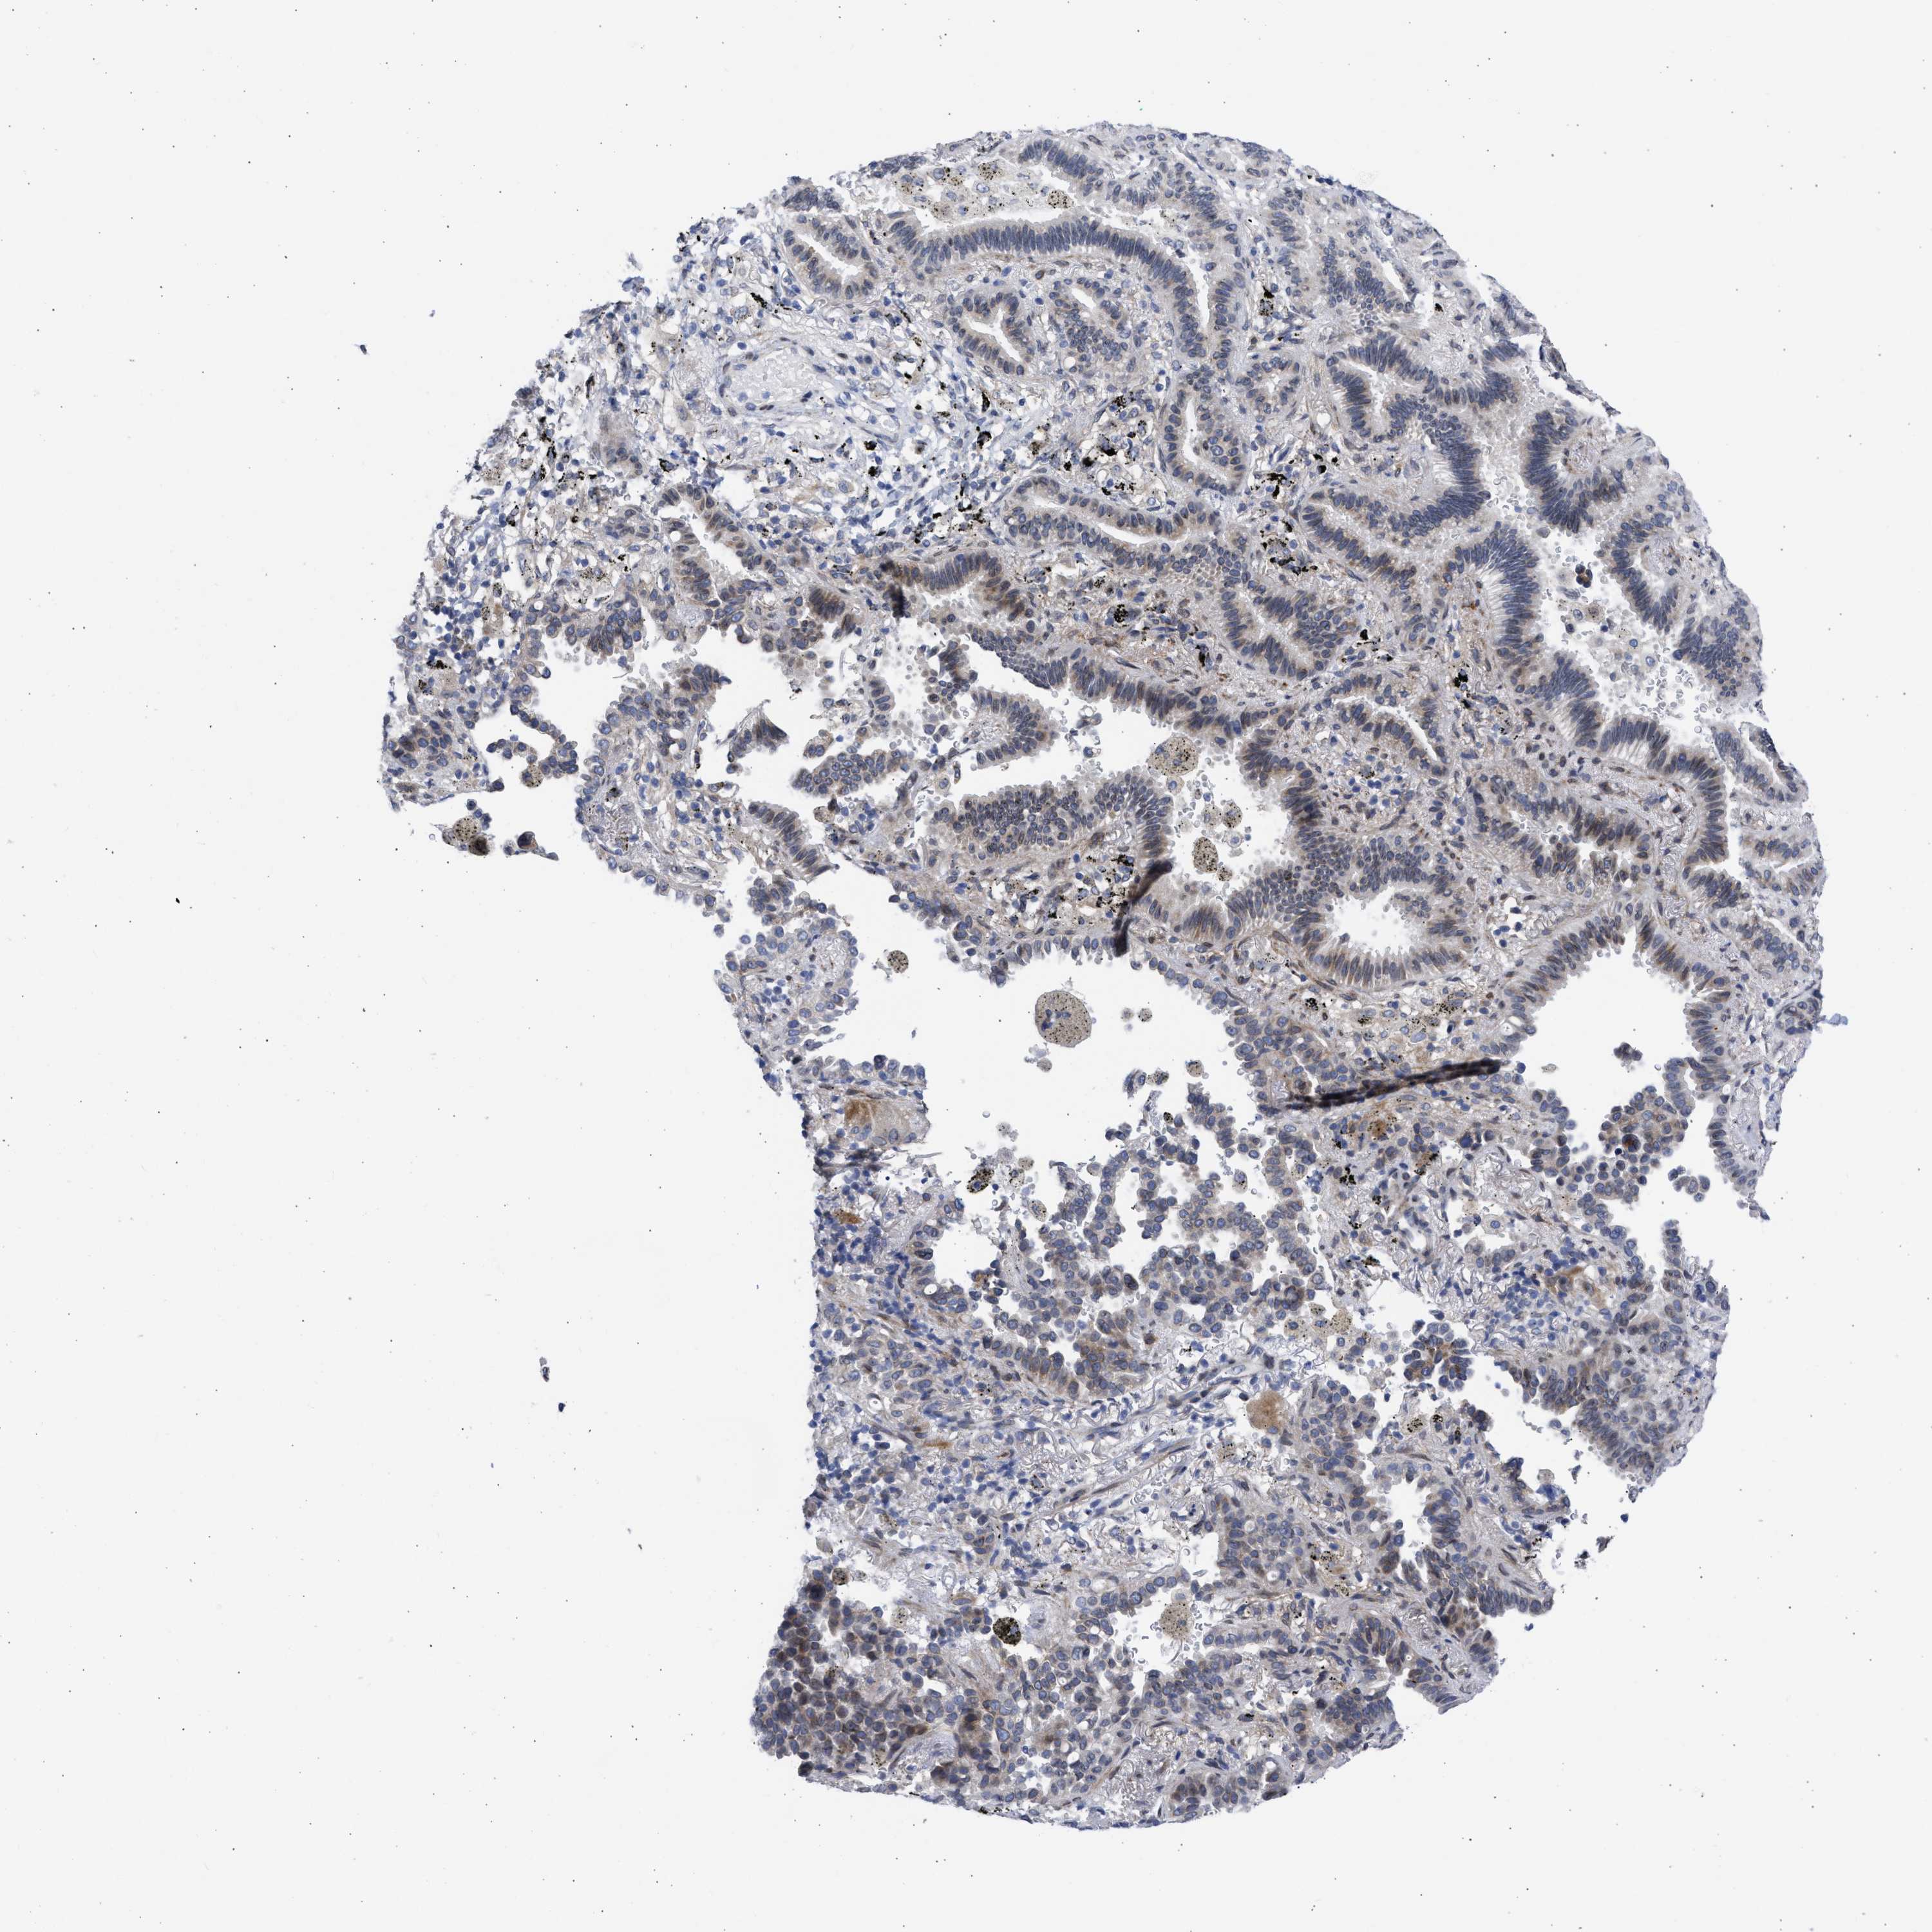

CANCER LUNG CANCER Show tissue menu

Lung cancer

Human cancer

Lung adenocarcinoma

Lung squamous cell carcinoma